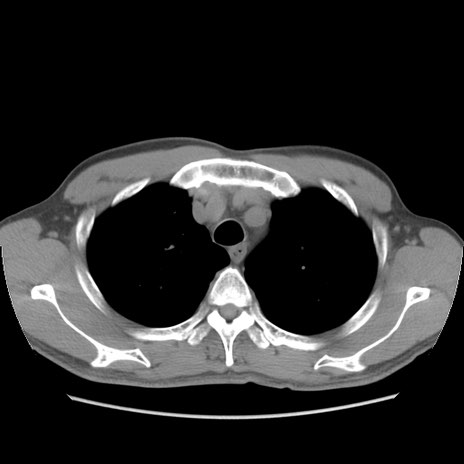

症例56 CT(横断像)

脂肪ウインドウ